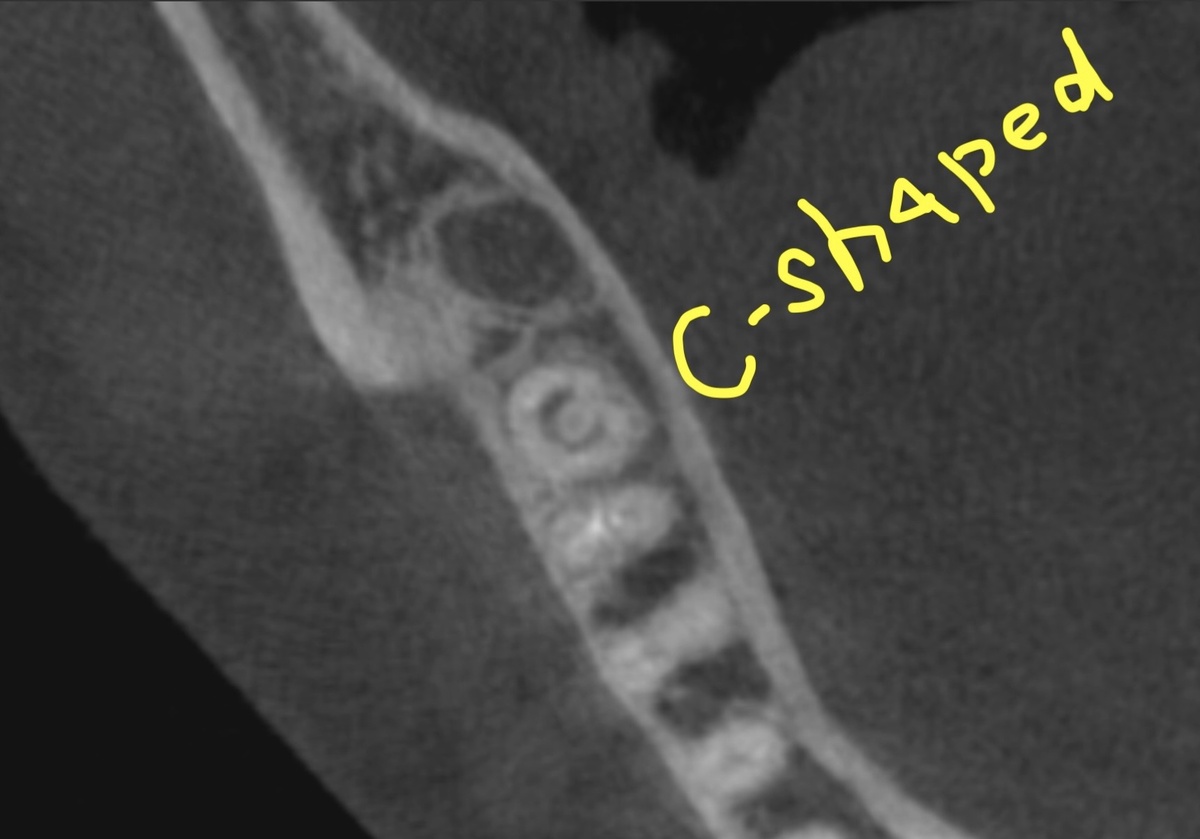

C-shaped каналы в 37 зубе

C-shaped (С-образная конфигурация) - это анатомическая аномалия корневых каналов, встречающаяся в 10-45% нижних вторых моляров у азиатского населения и в 2-8% у европейского.

Вместо отдельных круглых каналов - один канал в форме буквы С. На снимке КТ прекрасно видно, о чём я говорю.